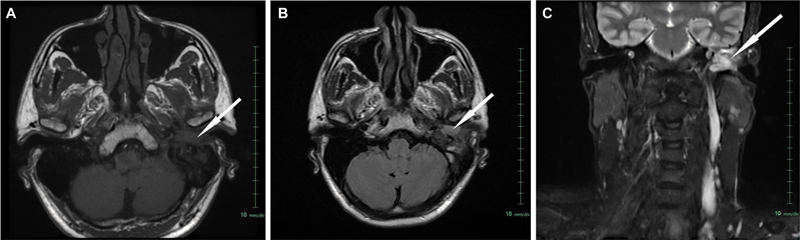

Neuroendocrine tumors of the middle ear are rare, comprising of less than 2% of primary tumors of the ear. The clinical and imaging findings of these tumors are nonspecific, and histological and immunohistochemical findings are confirmatory. Herein, we present a case of 48-year-old male, presenting with chief complaints of hearing loss of left ear with foul smelling discharge, with the initial clinical impression of otomastoiditis of the middle ear with cholesteatoma and being operated for the same, the final histopathology report inferred it as well-differentiated neuroendocrine tumor grade 1 with Ki-67 index less than 2%. Immunohistochemical examinations demonstrated positive staining of the tumor cells for cytokeratin, synaptophysin and chromogranin A, and negative for smooth muscle actin, desmin, S-100. The biochemical investigations showed raised serum chromogranin A levels. Based upon the findings on anatomical imaging modalities including high-resolution computed tomography temporal bone and magnetic resonance imaging paranasal sinuses (MRI PNS), the lesion was inferred inoperable due to involvement of dura of petrous apex, and therefore he was referred for consideration of peptide receptor radionuclide therapy (PRRT). MRI PNS also showed involvement of the horizontal part of facial nerve, indicating local aggressiveness of the tumor. 68 Ga-DOTATATE-PET/CT showed high-grade somatostatin receptor expressing soft tissue lesion involving middle ear and external auditory canal (Krenning's score 4), with low-grade metabolic activity on 18 F-FDG-PET/CT. The post-therapy scan following 177 Lu-DOTATATE PRRT, showed abnormal tracer concentration at the described site. Due to extreme rarity of this disease entity, it is important to accrue data for accurate diagnosis, proper management, and follow-up.